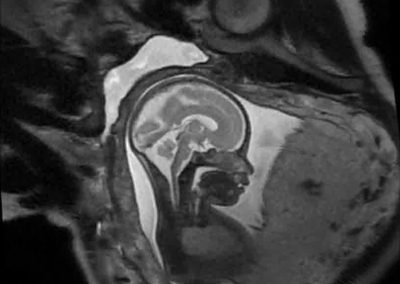

L’Université Paris Cité franchit une nouvelle étape dans le domaine de l’imagerie médicale anténatale avec l’acquisition d’un système d’Imagerie par Résonance Magnétique (IRM) 1,5T ARTIST™ de GE HealthCare. Cet équipement de pointe renforce les capacités de la Plateforme LUMIERE à l’hôpital Necker-Enfants malades, plateforme intégrée de soins, de recherche clinique et d’enseignement en imagerie médicale de la femme enceinte, du fœtus et du placenta.

Depuis 2020, la Plateforme LUMIERE offre aux femmes enceintes volontaires, entre 16 et 36 semaines d’aménorrhée et suivies à l’hôpital Necker-Enfants malades, la possibilité de participer activement à l’avancée de la recherche en médecine fœtale, tout en bénéficiant d’une IRM fœtale au cours de leur grossesse, réalisée dans un cadre sécurisé et encadré.

L’inclusion de ces patientes, depuis leur accueil jusqu’à la réalisation des examens d’imagerie, puis l’analyse des images et l’interprétation des résultats par des équipes expertes, enrichit une base de données structurée, unique au monde, au service de la recherche et de l’innovation en imagerie anténatale et en médecine fœtale.